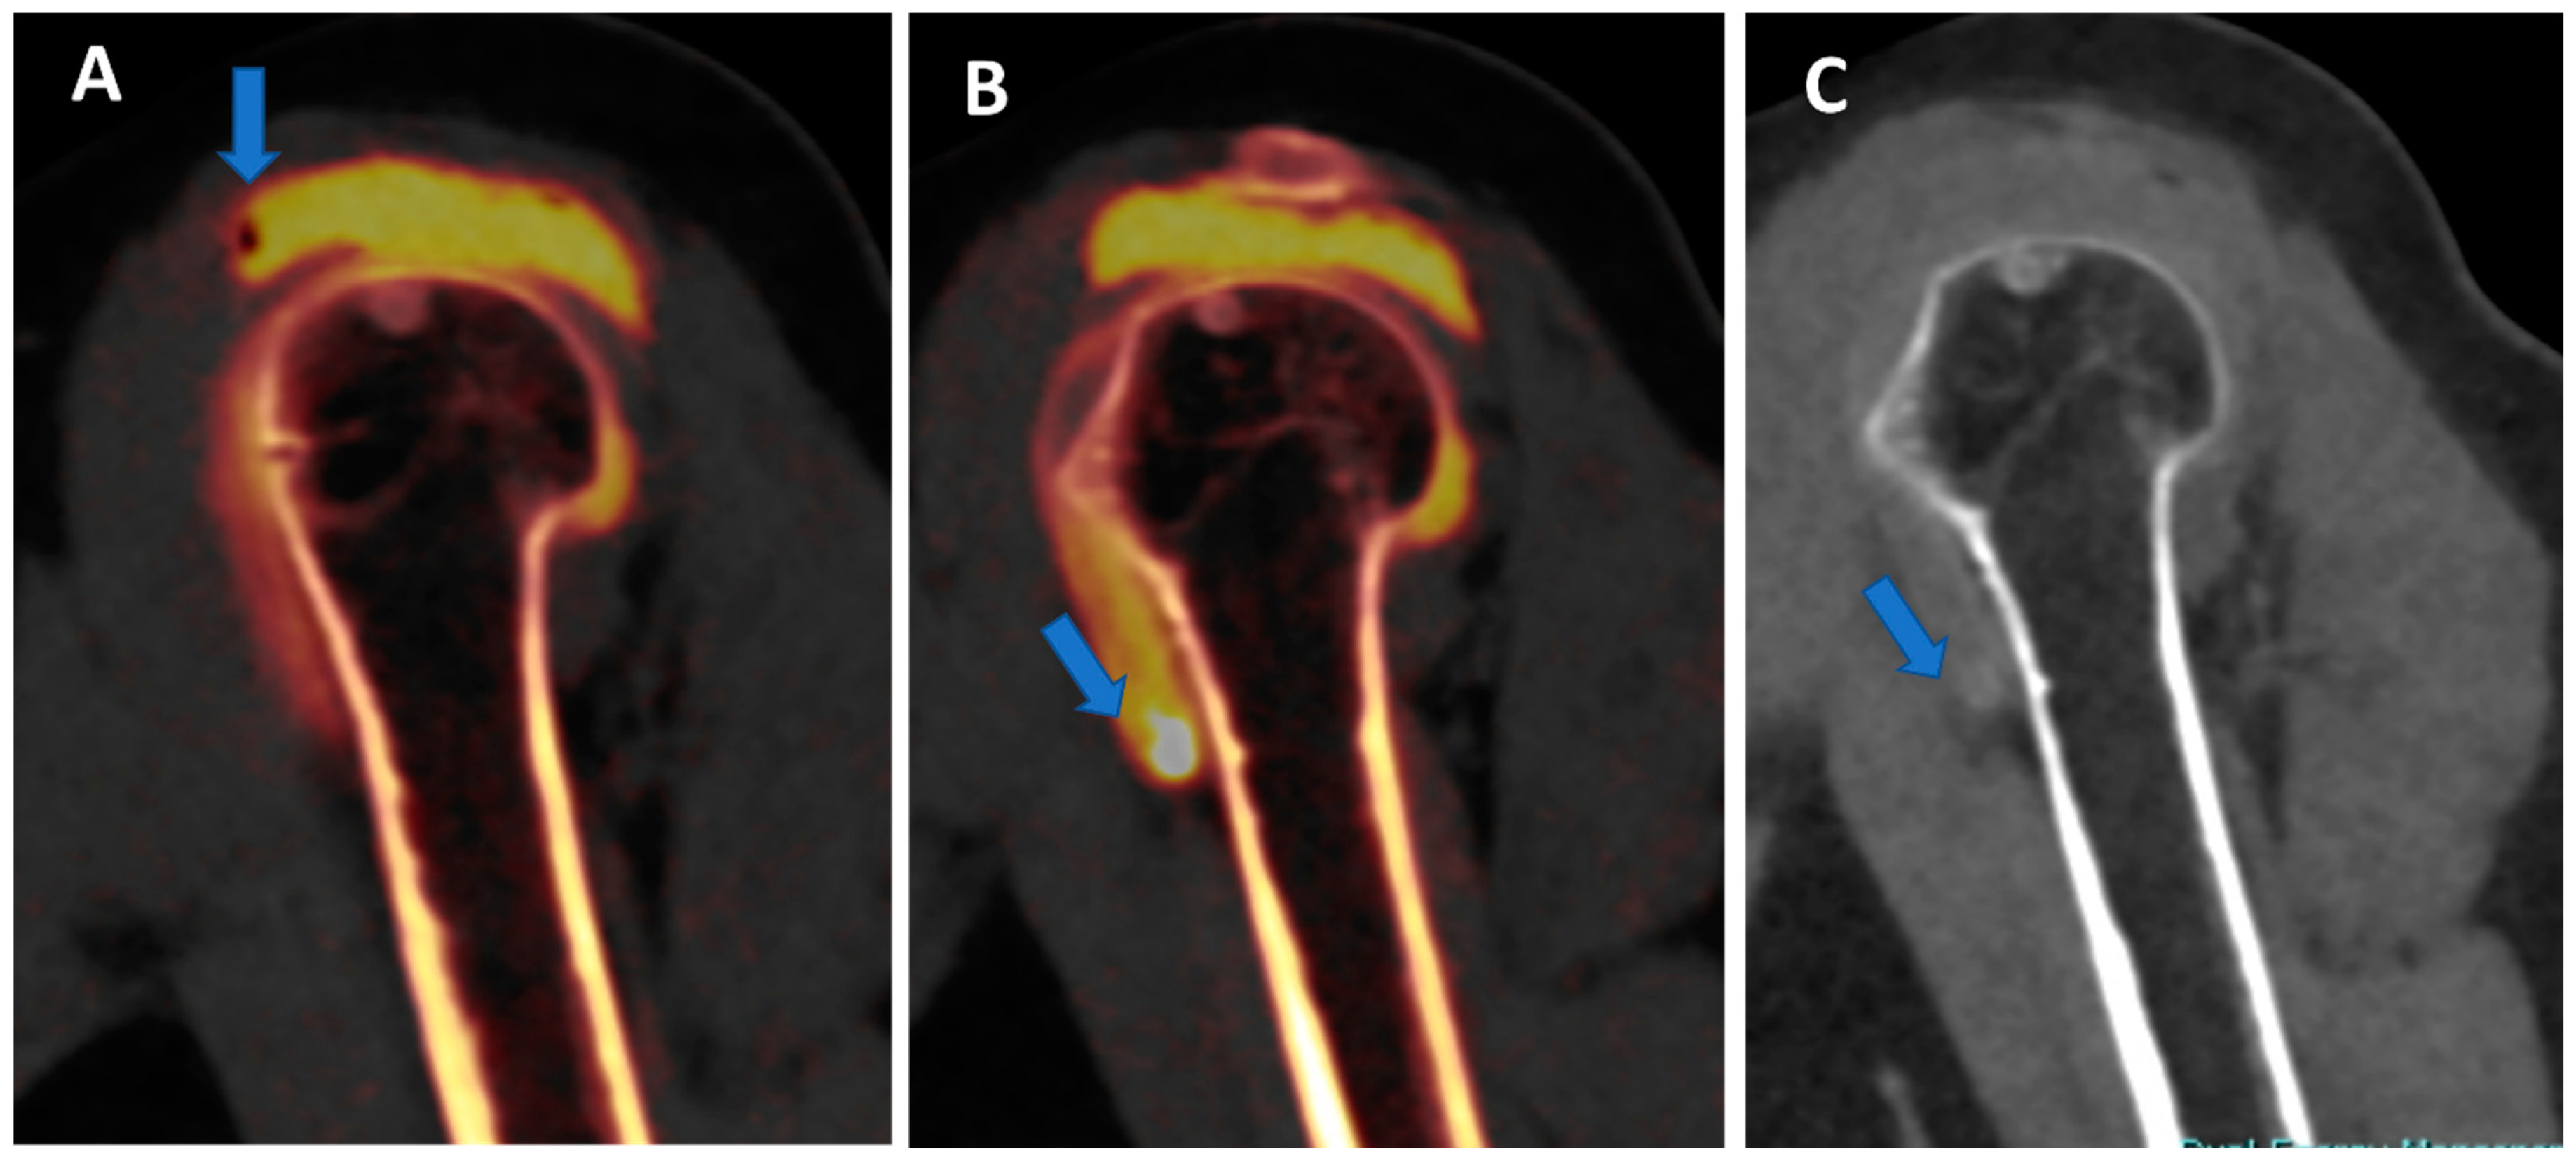

Figure 6. Traumatic anterior shoulder dislocation with rotator cuff complete tear and Hill Sachs lesion. On the 2D 1 mm axial and coronal reconstructed VNCa images (A,B), a subtle depression of the posterior aspect of the humeral head is visible, with mild edema coded in green on the superimposed map (arrow). The 3D VNCa image (C) clearly shows the passage of contrast material in the sub-acromial space (arrow). On the coronal 1 mm reconstructed iodine map image (D), the complete rupture of the rotator cuff is beautifully confirmed (arrow). On the sagittal LNC images (E,F), it is possible to identify (arrow on (F)) and quantify (ROI on (E)) the presence of atrophy of the muscle belly.